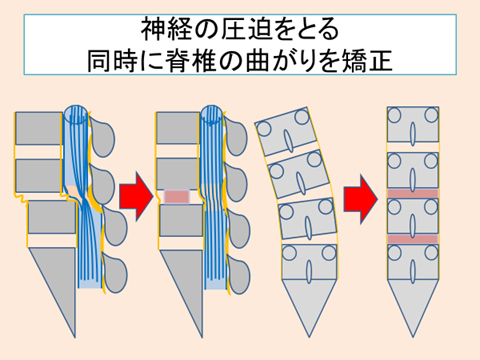

a3f1e84f-s.jpg。骨粗鬆症性椎体骨折に対する脊柱再建術 | 成尾整形外科病院。胸椎・腰椎の疾患 | 聖マリアンナ医科大学 横浜市西部病院。【送料込】 砕米24キロ 割れた米 飼料米 くず米 エサ米 鳥の餌。